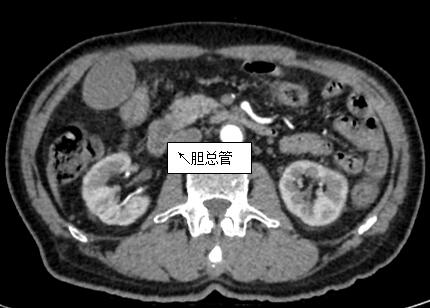

69歲王姓患者,因“發(fā)現(xiàn)無痛性黃疸1月”入院,根據(jù)患者病史,患者診斷傾向于壺腹部腫瘤所致梗阻性黃疸。予以完善腹部CT及上腹部MRI加MRCP均顯示肝內(nèi)外膽管擴(kuò)張,未發(fā)現(xiàn)明顯膽管,胰腺及十二指腸乳頭部腫瘤,且患者CA199正常。以前醫(yī)院未引進(jìn)超聲內(nèi)鏡,這類患者到此就遇到診斷瓶頸。此患者經(jīng)過消化內(nèi)科張丹霞副主任醫(yī)師完善超聲內(nèi)鏡檢查后,可以清楚顯示膽總管下段壁內(nèi)軟組織占位。患者通過超聲內(nèi)鏡檢查診斷明確,轉(zhuǎn)至肝膽外科行手術(shù)治療。

上腹部CT圖片